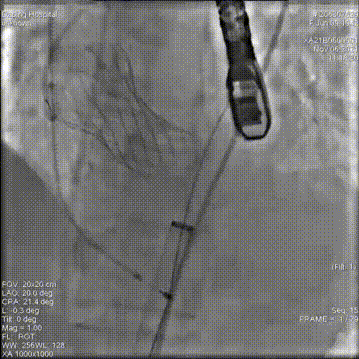

术后造影

术后压差14mmHg,钙化一侧微量反流,瓣膜正常工作,血流动力学即刻得到改善。